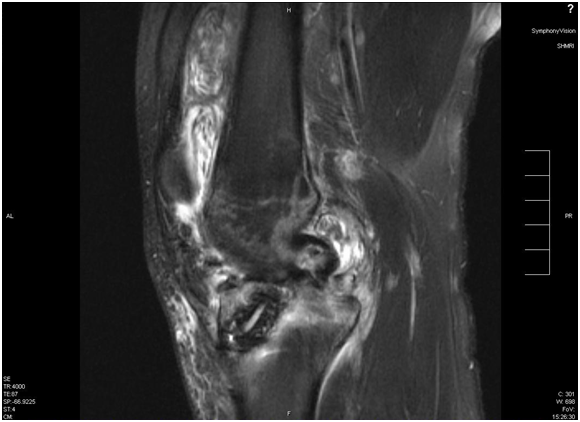

A 24-year-old white male sustained a right medial meniscal tear and anterior cruciate ligament (ACL) injury in January 2006. He was wrestling with some friends over a hard surface (concrete), when he sustained a twisting type injury to his right knee and felt a pop. He underwent a right arthroscopy for ACL reconstruction with a bone-tendon-bone cadaveric ACL allograft on September 16th, 2006. We could not determine information on antibiotic prophylaxis. His rehabilitation was unremarkable until January 2007, when he developed pain in his right knee, a new pop on his knee, with progressive swelling and joint effusion. He received a trial of physical therapy and nonsteroidal anti-inflammatory drugs (NSAIDs), with no resolution. He was evaluated by his orthopedic surgeon, who performed an arthrocentesis, relieving the swelling and pain. The fluid was not cultured. However, the swelling and the pain came back. Two more arthrocentesis were performed on February 5th and 15th. Both cultures from synovial fluid recovered Candida glabrata, which was believed to be responsible for his effusion and knee pain (cell count and differential were not available). He was started on IV caspofungin (loading dose: 70mg, maintenance: 50mg IV every day), with persistent swelling, pain with constant range of motion, and instability in his knee. He denied any numbness or tingling of the leg. He denied any other aches, bumps, and bruises. He also denied any current fever, chills or night sweats. His past medical history is unremarkable. He was not taking any medication in addition to caspofungin. He did not have any allergic reactions. He worked as a welder. He smokes two to three cigarettes per day, and denied alcohol or intravenous drug use (IVDU). His physical examination revealed a well-developed white male in no acute distress. His right lower extremity revealed a moderate effusion of the right knee, with considerable soft tissue swelling and mildly warmer than the left knee. Range of motion was from full extension to approximately 115 degrees flexion. The knee has a positive Lachman sign, the McMurray test was difficult to assess, and muscle strength was normal. He had a brisk capillary refill, and conserved sensation to light touch throughout his extremities. Surgical incisions from previous arthrocentesis did not show evidence of infection. Except for mild thrombocytosis (platelet count: 430x106/mL), complete blood count and basic chemistry were within normal limits. Erythrocyte sedimentation rate was 35mm, and C-reactive protein was 2.5mg/dL. An MRI showed a chronically ruptured ACL graft, with resorption of the graft, proximal retention screws extending into the joint space, and joint effusion (Figures 1-3). X-ray imaging showed osteolysis at the level of the tibial tunnel. An Infectious Diseases consultation was obtained, after concern for C.glabrata septic arthritis and possible osteomyelitis. Caspofungin was continued, and a new arthrocentesis was performed (cell count or differential were not performed).

Figure 2 Effusion with multiple loose bodies on suprapatellar pouch and septum formation.